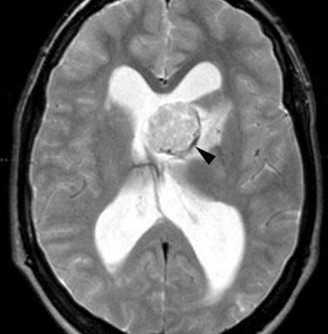

(а) МРТ, Т2-ВИ, аксиальный срез: у того же пациента в левом переднем роге определяется образование дольчатой структуры гиперинтенсивного по отношению как к белому, так и к серому веществу сигнала.

В структуре субкортикального белого вещества под кортикальными туберсами наблюдаются несколько зон гиперинтесивного сигнала в форме «языков пламени».

(б) MPT, FLAIR, аксиальный срез: у того же пациента определяется, что образование дольчатой структуры, расположенное в области переднего рога левого бокового желудочка, не обтурирует боковой желудочек.

Зоны гиперинтесивного сигнала в форме «языков пламени» в структуре белого вещества (БВ) под кортикальными туберсами на данной последовательности визуализируются лучше.